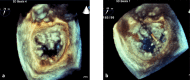

Cardiovascular imaging has significantly evolved since the turn of the century. Progress in the last two decades has been marked by advances in every modality used to image the heart, including echocardiography, cardiac magnetic resonance, cardiac CT and nuclear cardiology. There has also been a dramatic increase in hybrid and fusion modalities that leverage the unique capabilities of two imaging techniques simultaneously, as well as the incorporation of artificial intelligence and machine learning into the clinical workflow. These advances in non-invasive cardiac imaging have guided patient management and improved clinical outcomes. The technological developments of the past 20 years have also given rise to new imaging subspecialities and increased the demand for dedicated cardiac imagers who are cross-trained in multiple modalities. This state-of-the-art review summarizes the evolution of multimodality cardiac imaging in the 21st century and highlights opportunities for future innovation.